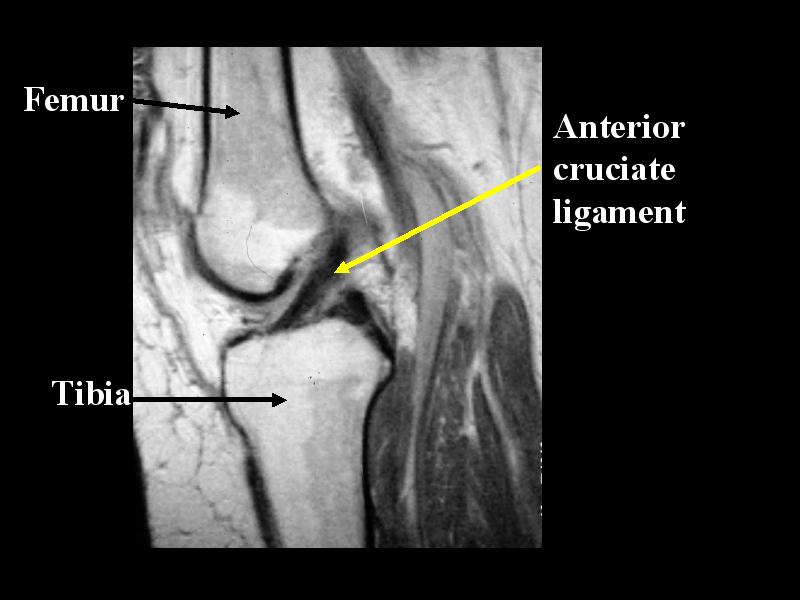

MS 200 MR NORMAL 69